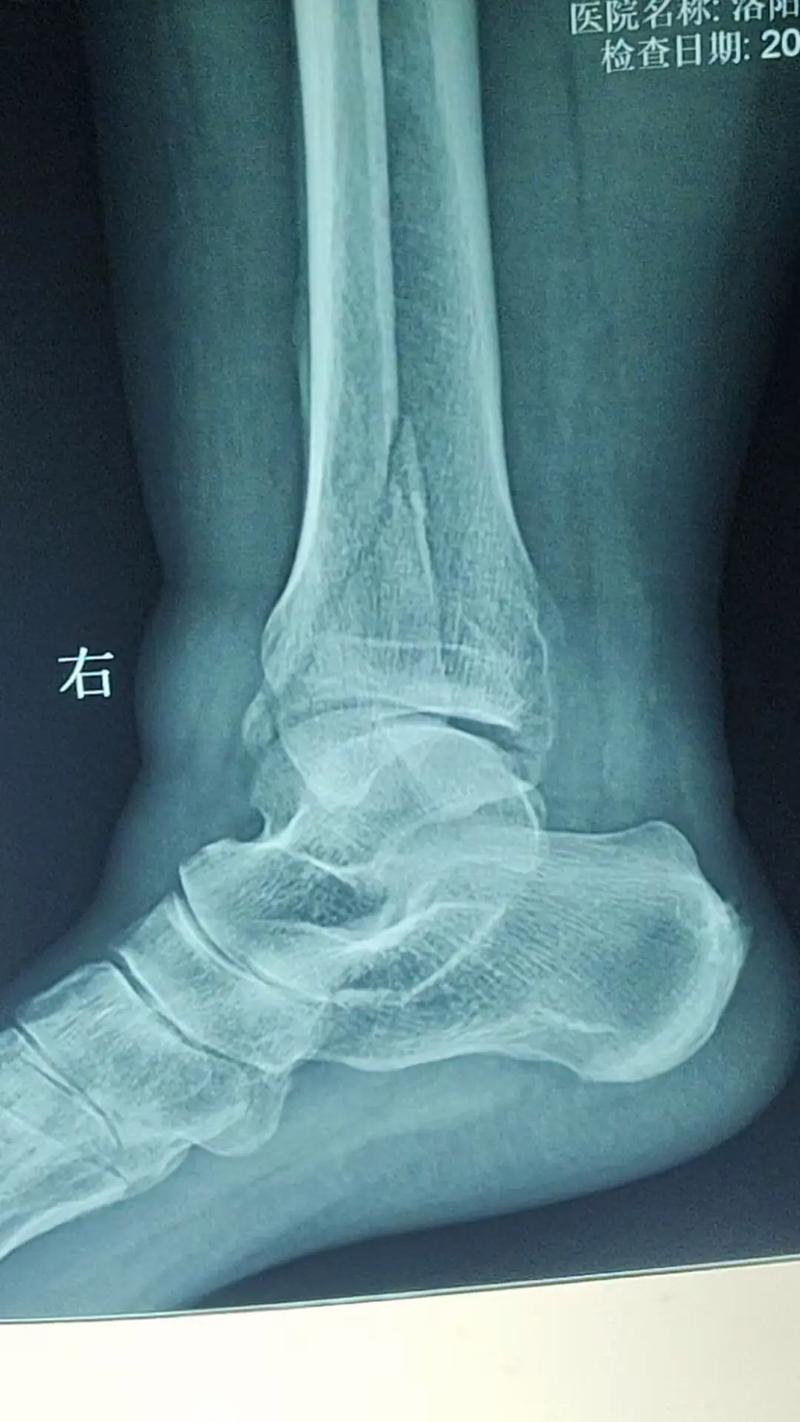

这种方位失调,最常引发的是四肢末端骨折,如手指、脚趾或是手腕、踝关节的扭伤骨裂、如果正西方位有动土施工,或者家中的洗衣机、音响等产生剧烈震动的电器安置于此,会催动三碧木的暴虐之气、居住者往往会在运动中意外受伤,或是由于骨质脆性增加,在微小的碰撞下发生骨裂。